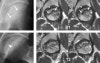

- MRI

대퇴골두와 경부에 걸쳐 부분적 또는 광범위하게 T1에서는 저신호 강도, T2 또는 지방 억제 영상에서는 고신호 강도로 나타나는 경계가 불명확한 이상소견을 보입니다(전형적인 골수 부종 소견).

연골하 골판 부위에 평행하게 주행하면서 T1에서는 저신호 강도, 다른 강조 영상에서는 다양한 신호 강도로 나타나는 이상 신호 강도선(연골하 골절선, MR crescent sign)을 관찰할 수 있습니다.

대부분 대퇴골두의 전상방에서 관찰되지만 일부에서는 후상방에서 관찰되기도 합니다.

골수 부종과 연골하 골절 소견은 대퇴골두 무혈성 괴사에서도 관찰되기 때문에 감별진단에 주의해야 합니다.

MRI : subchondral fatigue fracture of the femoral head